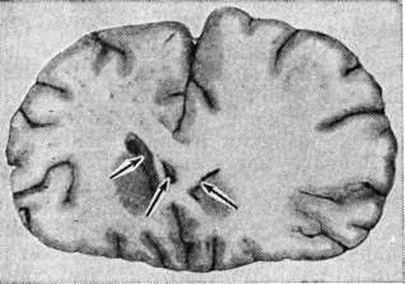

Патологическая анатомия. Макроскопически отёк и набухание головного мозга характеризуются рядом признаков: влажностью и помутнением поверхности, увеличением объёма, повышенной дряблостью (оводнённостью) мозгового вещества, имеющего желтовато-розовую окраску, нечёткостью границ между серым и белым веществом (рисунок). В связи с общим увеличением объёма головного мозга обнаруживаются глубокие вдавления в области полушарий мозжечка и выбухание его миндалин, что является морфологическим признаком странгуляции стволовых отделов в отверстии намета мозжечка. Однако отмечаются и различия признаков отёка и набухания. При преобладающем осложнённых имеет место полнокровие и отёчность мягкой оболочки головного мозга, с поверхности которой наряду с кровью стекает прозрачная жидкость. В желудочках мозга отмечается повышенное количество цереброспинальной жидкости. Вещество мозга на разрезах представляется избыточно влажным, легко режется ножом, с поверхности разреза стекает прозрачная жидкость. При преимущественном набухании структурных элементов головного мозга мягкие мозговые оболочки, напротив, суховаты, вещество мозга плотное, нож прилипает к поверхности разреза. В желудочках мозга цереброспинальная жидкость отсутствует или содержится в незначительном количестве, желудочки щелевидны.